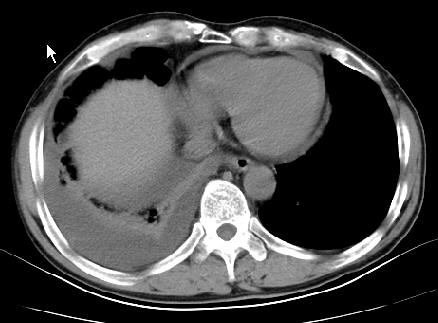

以下是引用草之原在2009-5-2 19:29:00的发言:[br]1.考虑右侧中心型肺ca纵膈淋巴结转移,双侧胸腔积液及右侧叶间裂积液,心包积液。[br]2.两肺上叶病灶,纵膈窗显示部分病灶硬化,考虑:结核。[br][br] [br]

以下是引用ct诊断高手在2009-5-2 19:08:00的发言:[br]我考虑右侧中央型肺癌 伴右肺节段性不张,两肺及纵隔淋巴结转移,右侧胸腔积液。

以下是引用zjzjr在2009-5-2 20:16:00的发言:[br]肺结核,转移瘤.纵隔淋巴结转移或淋巴瘤,右侧包裹性积液、斜裂积液。心包积液。